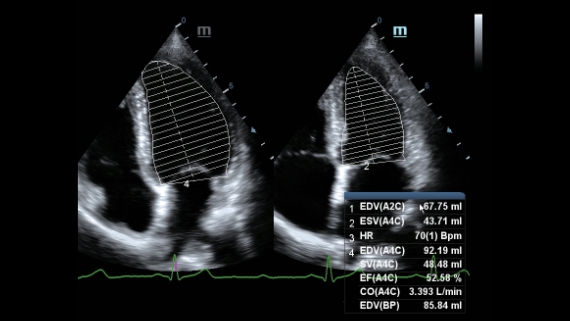

Klinische Bilder